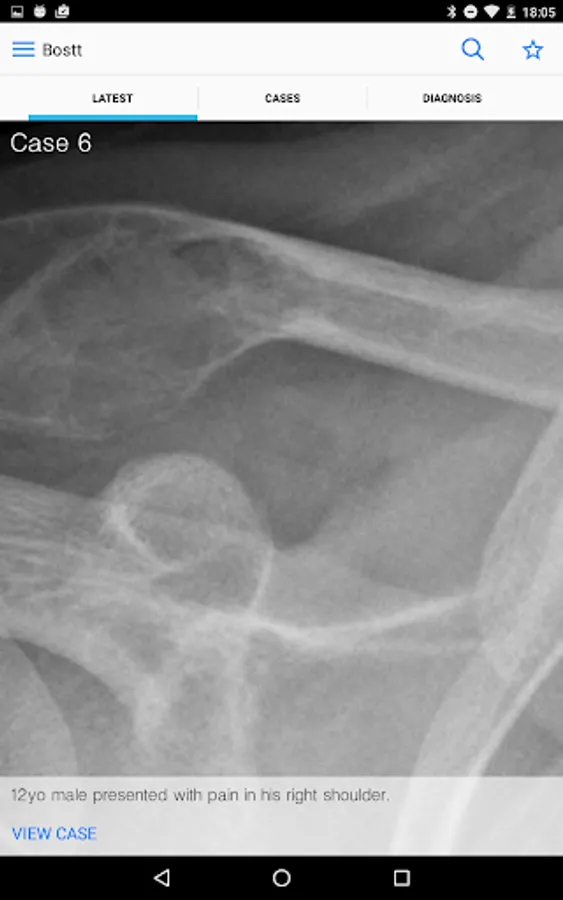

BoSTT brings the user a real experience of frequent and rare, typical and more unusual cases of bone and soft tissue tumours. Each case has a clinical history, high resolution radiology and pathology images, diagnosis, treatment and learning points.